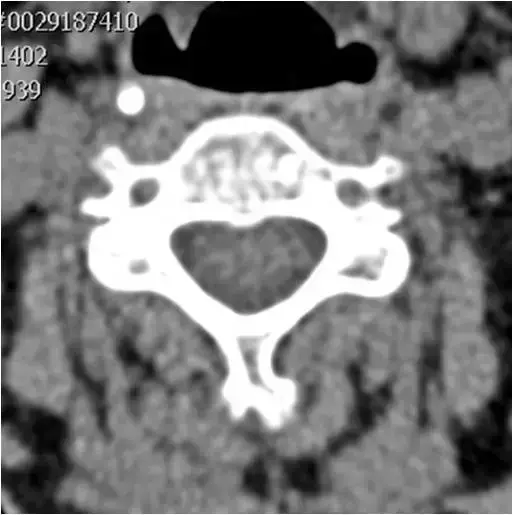

图19:通过上颈椎椎体的轴向CT图像。